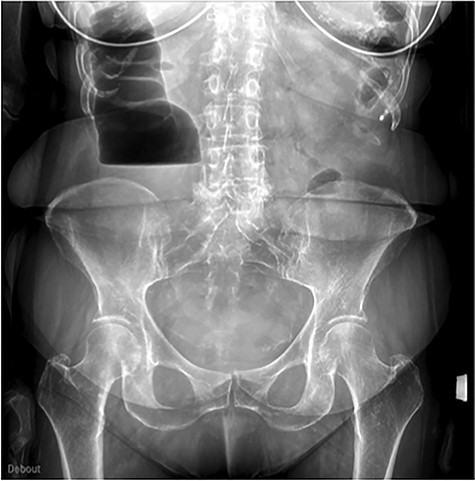

The scanner demonstrated a colonic occlusion resulting from an incarceration, which was diagnosed as a hernia of Bochdalek containing the hepatic angle of the colon (Fig. 2–4).

: CT scan images demonstrating a right diaphragmatic hernia containing intestine.